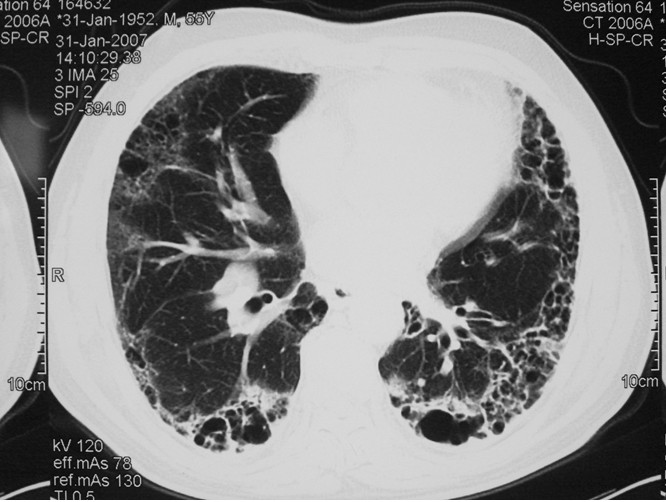

肺纤维化是以成纤维细胞增殖及大量细胞外基质聚集并伴炎症损伤、组织结构破坏为特征的一大类肺疾病的终末期改变,也就是正常的肺泡组织被损坏后经过异常修复导致结构异常(疤痕形成)。绝大部分肺纤维化病人病因不明(特发性),这组疾病称为特发性间质性肺炎(IIP),是间质性肺病中一大类。而特发性间质性肺炎(IIP)中最常见的以肺纤维化病变为主要表现形式的疾病类型为特发性肺更多>>